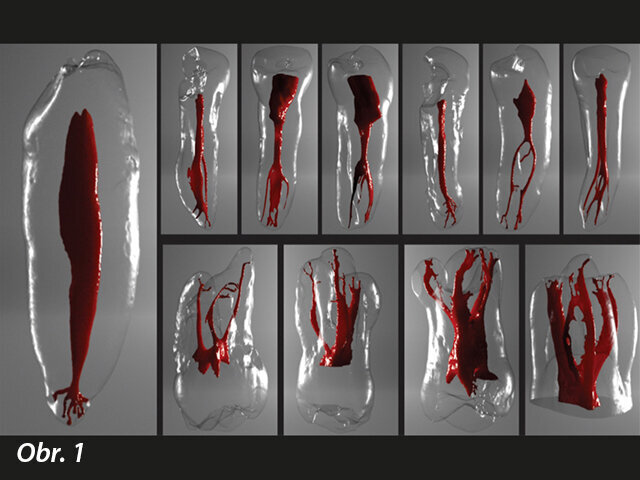

Chlornan sodný má antimikrobiální účinek a rozpouští tkáň, ale míra jeho účinnosti odstraňování bakterií závisí na mnoha faktorech, mezi kterými hraje důležitou roli to, zda pronikne celou délkou kanálku, a také výměna tekutin v prostoru kanálku. Anatomie kořenových kanálků, systém aplikace výplachu, hloubka umístění, vlastnosti roztoku a jeho objem ovlivňují jeho výplachové působení. Anatomická komplexita zubů byla široce zkoumána v literatuře a systém kořenových kanálků byl obzvlášť zajímavý s ohledem na variabilitu jeho anatomie (obr. 1).

Komplexnost systémů kořenových kanálků ukazuje na oblasti, které nemohou být dosaženy mechanickou preparací